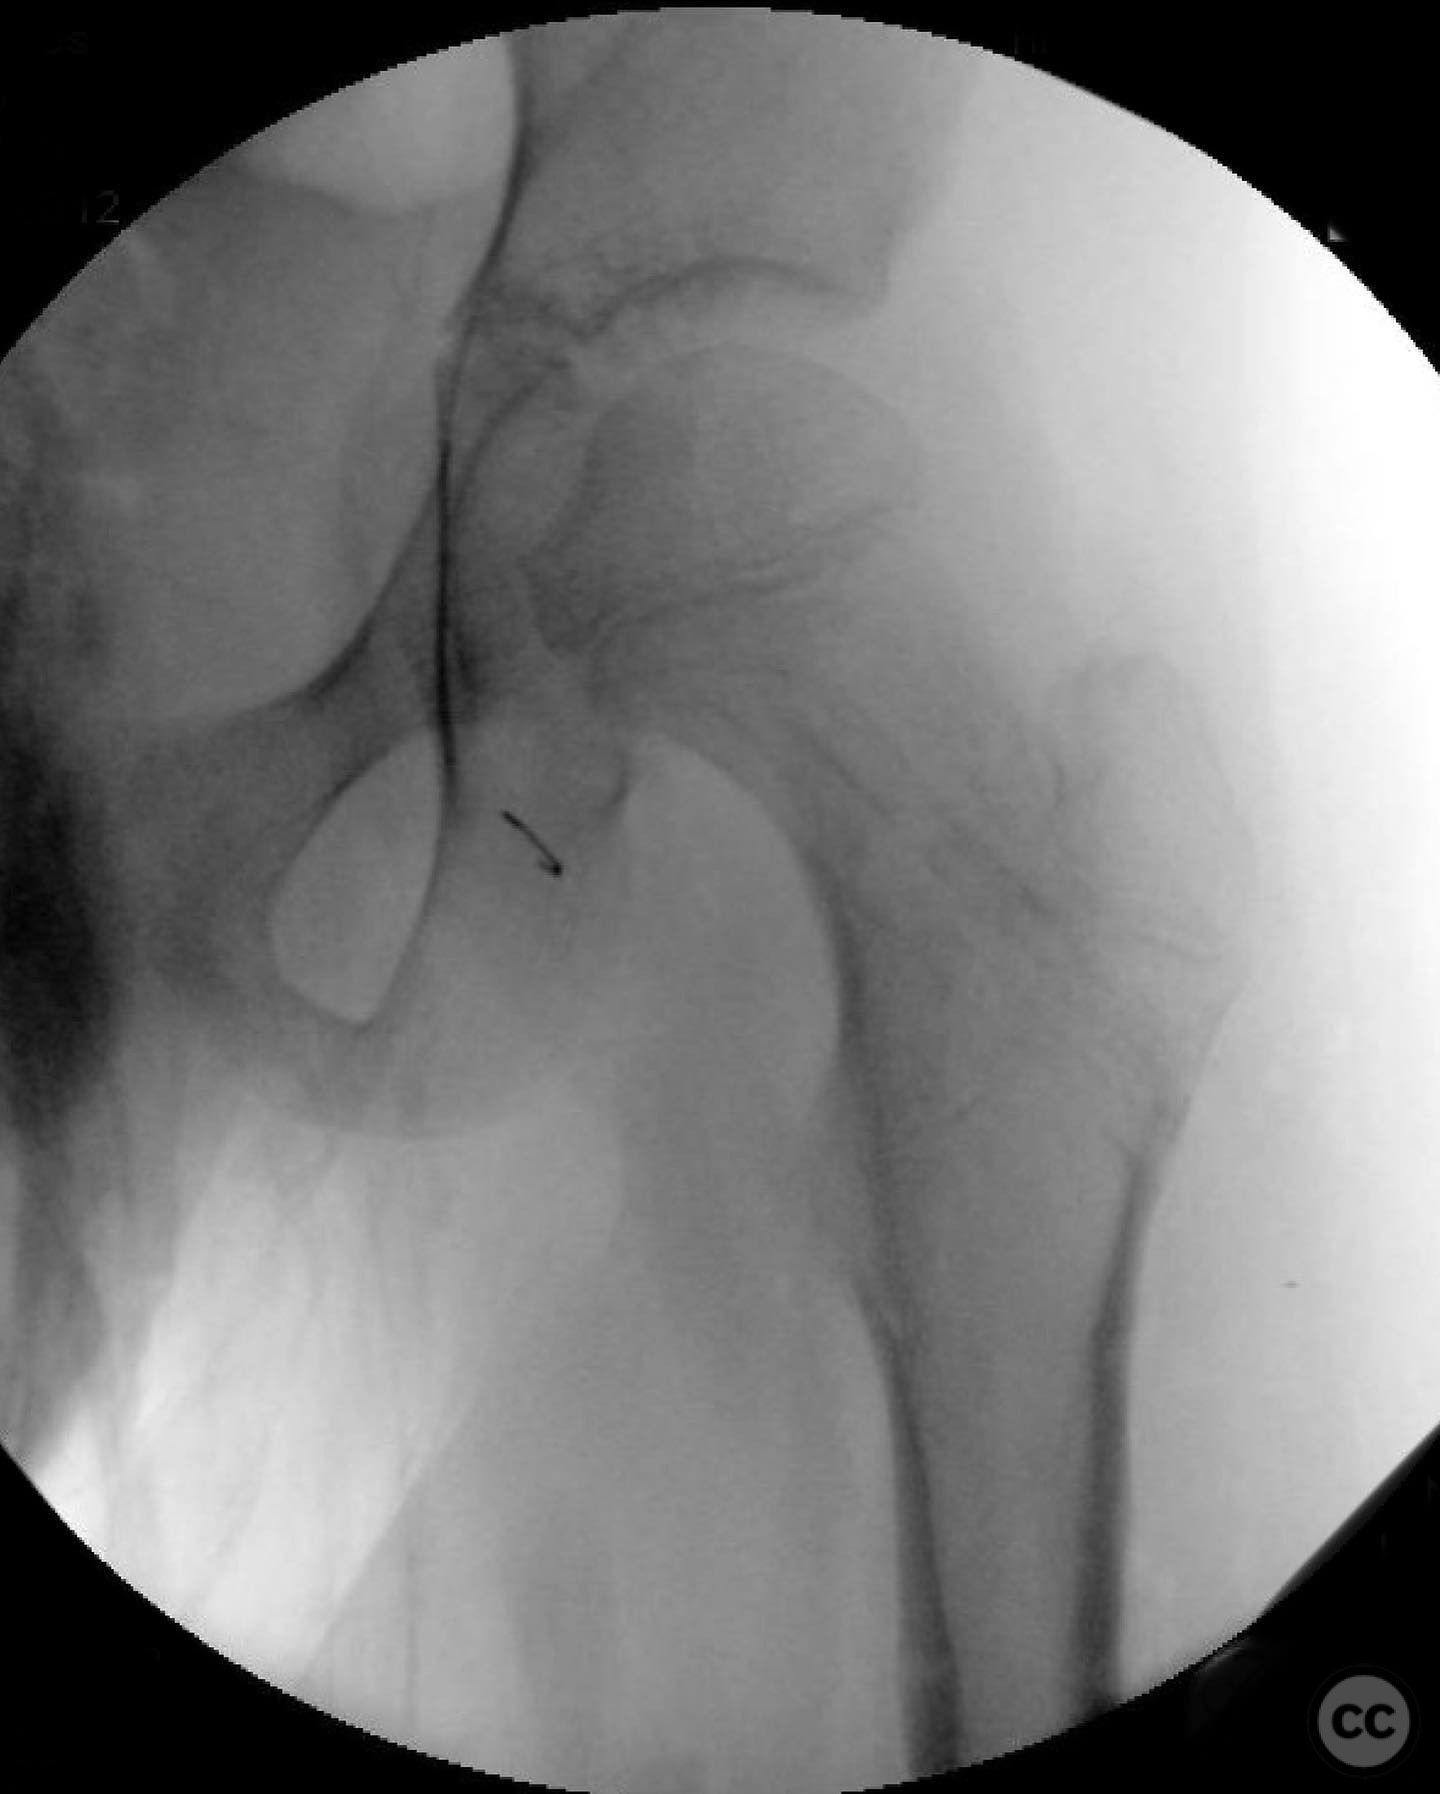

Patient positioning:  Supine position on a radiolucent table to facilitate intraoperative imaging and access to the femoral neck.

Anatomical surgical approach:  A modified Smith-Petersen approach was utilized, involving an incision along the anterior aspect of the hip, allowing for direct visualization of the femoral neck. Subperiosteal dissection was performed to expose the fracture site without compromising the surrounding musculature. A separate lateral approach was employed for the application of fixation devices.

Operative remarks:

The surgeon emphasized the importance of achieving a high-quality reduction and stable fixation due to the displacement pattern of the fracture. A meticulous surgical approach was critical to avoid malreduction, which is not well-tolerated in pediatric patients. The modified Smith-Petersen approach provided excellent visualization for anatomic reduction, minimizing soft tissue damage.